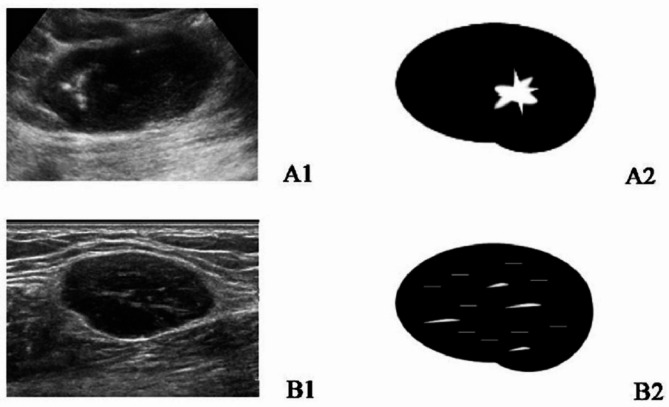

Results: A total of 41 patients were enrolled in the study, comprising 29 with HV-type, 4 with PC-type, and 8 with a mixed type. All patients presented with enlarged lymph nodes (LNs) characterized by a solitary mass, well-defined margins, and increased cortical thickness. Among these, 95.12% (39/41) exhibited an indistinct corticomedullary interface. Additionally, 41.46% (17/41) showed eccentric or asymmetrical cortical thickening, while 58.54% (24/41) demonstrated complete effacement of the fatty hilum. Approximately 24.39% (10/41) of cases exhibited macrocalcification, and 56.10% (23/41) displayed short linear hyperechoic foci within the lymph nodes. Furthermore, patients with HV-type and mixed-type conditions exhibited more abundant blood flow signals compared to those with PC-type (75.86% vs. 25% vs. 87.50%, P = 0.018).

Conclusions: Ultrasound characteristics of UCD generally comprise sizable, solitary masses with clearly delineated borders, a thickened cortex, and disappearance of the fatty hilum. Principal imaging indicators encompass microcalcifications and short linear hyper-echoes. Ultrasound represents an effective and non-invasive modality for the early identification and diagnosis of UCD.